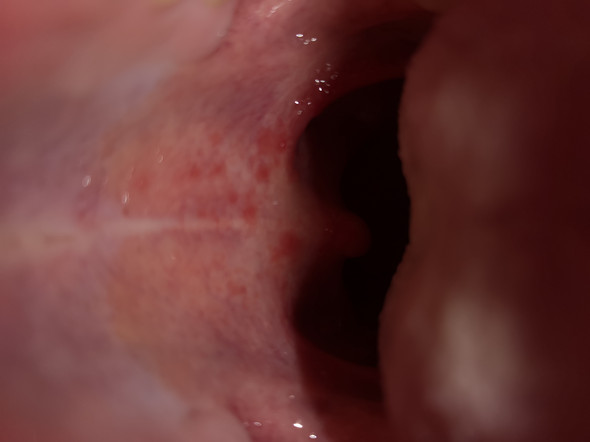

Hallo erst mal wieder mal schlaflos in Fürstenfeldfolgende Fragehabe seit zwei Wochen einen roten Fleck am harten Gaumenfast ne Gaumenhälfte grosswenn ich mit der Zunge drüberfahre ist die Stelle schmerzlosglatt und es fühlt sich so an als ob der Fleck rundherum eingerenzt wärwar beim zahnarztder hat mich zur hautärztin geschicktund die hat mir. Rote Flecken am Gaumen können verschiedene Ursachen haben. Der fleck fühlt sich glatter an als der Rest vom Gaumen ich war auch schon bei meiner Ärztin und sie meinte es wäre eine Verbrennung aber so lange bleibt doch keine verbrennung zu sehen.

Anfang August einen roten Fleck am gaumen der nicht weh tut immer noch gleich aussieht und ich auch keinerlei andere Symptome habe. Machen Sie jetzt den Test und beantworten Sie folgende 10 Fragen. Hallo seit knapp einer Woche habe ich eine geschwollene Stelle am Gaumen.

Heilendes Küssen Ihre Meinung zum Thema ist gefragt. Test rote Flecken am Gaumen. Das Vorhandensein roter Punkte am Gaumen gab in jedem Alter Anlass zur Sorge.

Manche dieser Flecken sind zwar störend aber harmlos während andere ein Zeichen für ein ernsteres gesundheitliches Problem sein können das genauer untersucht werden muss. Weiße Stellen können auch durch Wangenbeißen oder durch Reiben der Wangen oder Zunge auf einem scharfen Teil eines Zahns oder einer Zahnfüllung.